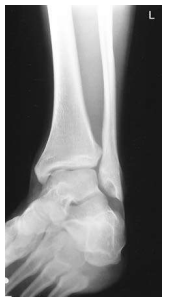

What ankle view is this?

Mortise